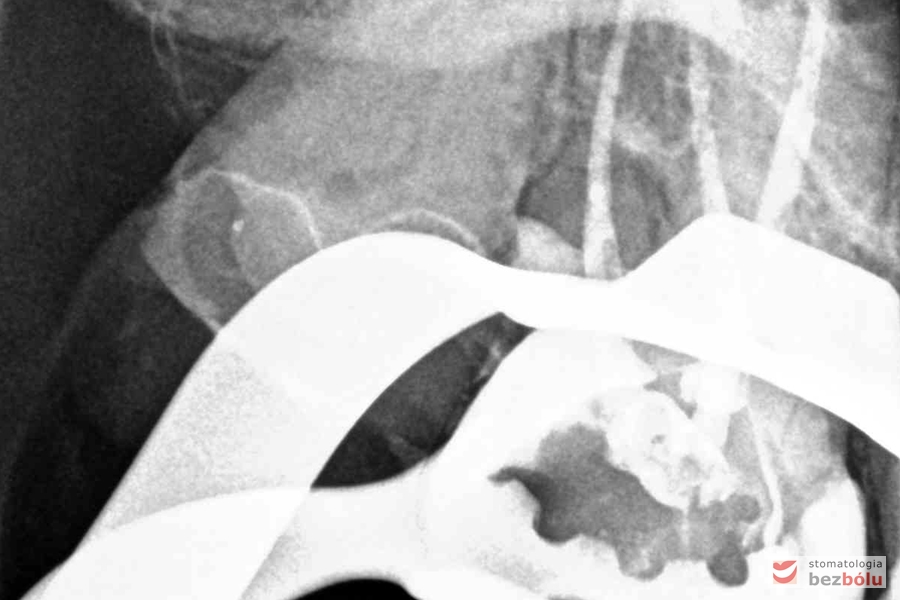

Radiowizjografia - jedynka górna prawa z niedopełnionym kanałem korzeniowym

Radiowizjografia – jedynka górna prawa z niedopełnionym kanałem korzeniowym